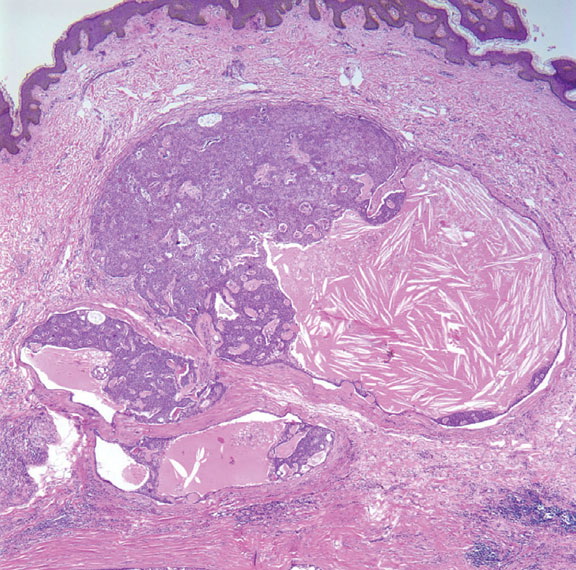

Solid cystic hidradenoma = الغدوم العرقي الكيسي الصلب